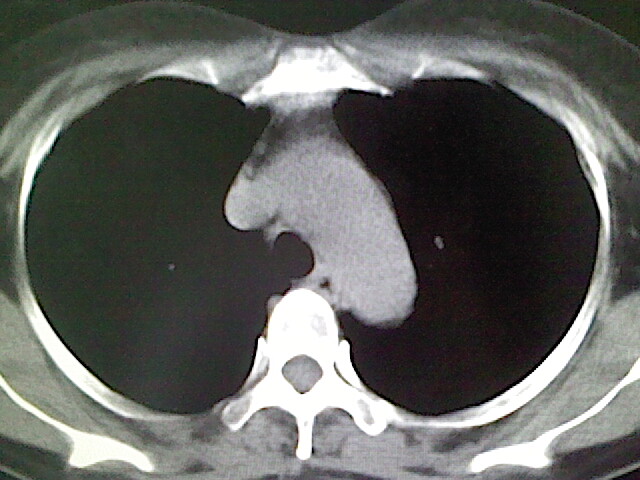

女,52岁,咳嗽,咳痰多日

左下肺陈旧纤维索条!

左肺舌段炎性改变

我见过几例,为炎症后纤维条索

慢性炎症后改变

考虑慢性炎性病灶粘连牵拉改变。

左肺舌叶纤维锁条病变。

左肺上叶下舌段炎症并局部胸膜反应。

左肺舌叶纤维索条影。

左肺舌叶段陈旧性病变

左肺舌段炎性反应。片子的质量太不好了。

左肺舌段炎性

炎性改变

左肺舌叶纤维索条影